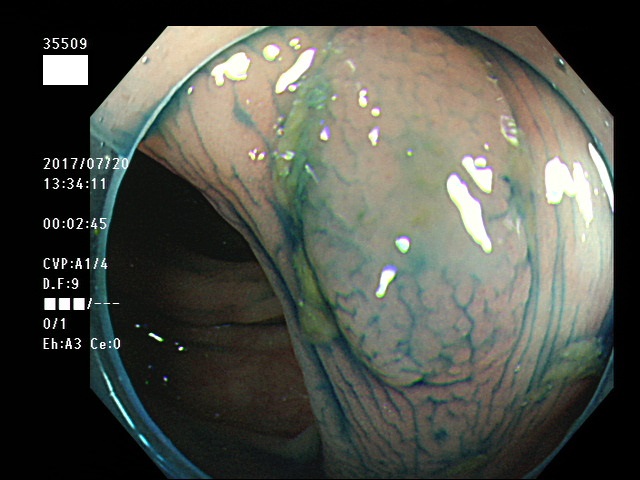

上記100名より抽出した平坦・陥凹型腺腫・SSAP(=癌化の危険が高いが見落としやすい病変)の内視鏡写真

35500 35501 35502 35506 35508 35509 35511 35514 35515 35516 35517 35520 35521 35522 35523 35524 35525 35526 35528 35532 35535 35536 35539 35542 35544 35545 35547 35548 35550 35553 35556 35559 35560 35561 35562 35563 35564 35567 35569 35570 35571 35578 35581 35584 35585 35587 35588 35589 35590 35592 35593 35594 35598 35599・・・・・の54名